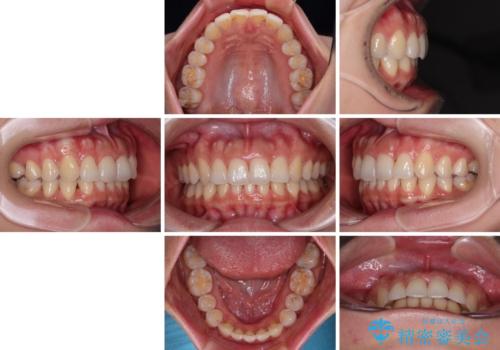

捻れた前歯をインビザラインで整える

- 捻れた前歯が飛び出しており、口が閉じにくいとのことで来院された患者様です。

出っ歯というわけではないものの、前歯の捻転により口唇が押し出されている状態でした。

親知らずを抜去し、歯列全体を後方に移動させつつ、IPR(歯と歯の間を削る)でスペースを獲得し、インビザラインを用いて叢生を解消しながら前歯の突出を改善することとしました。

骨格的に上下正中がずれていたため、奥歯がしっかりと噛み合うか心配でしたが、ずれているなりに、しっかりとした咬み合わせとなりました。